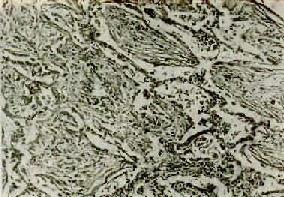

(1)肺肉质变:因吞噬细胞数量少或功能缺陷,渗出物不能被完全吸收清除时,则由肉芽组织予以机化(图9-17),病变部位肺组织变成褐色肉样纤维组织,称肉质变(carnification)。

图9-17 肺肉质变

肺泡腔内炎性渗出物已被结缔组织所替代